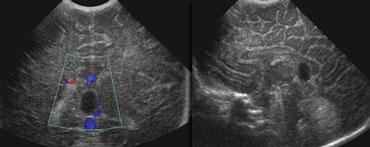

Hình bên trái là xuất huyết nội sọ độ 2.

Trên mặt cắt đứng ngang, chỉ nhìn thấy khoang vách trong suốt.

Cả hai não thất bên đều chứa đầy máu, nhưng không có giãn não thất.

Hình bên trái là cùng bệnh nhân sau 3 ngày.

Các não thất giãn rộng và có hình ảnh hình thành cục máu đông.

Não úng thủy thứ phát xảy ra vài ngày sau xuất huyết độ 2 không nên bị nhầm lẫn với xuất huyết độ 3.